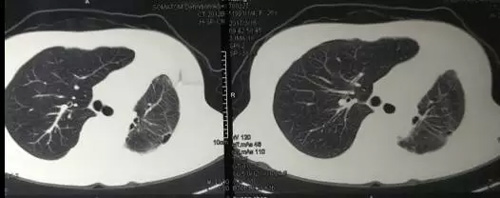

青年女性,因“胸闷气短1年”收入院。患者曾在外院多家医院就诊,误诊为“支气管哮喘”治疗半年余。就诊我院门诊胸部CT检查示左主支气管肿瘤。

入院时CT如图: